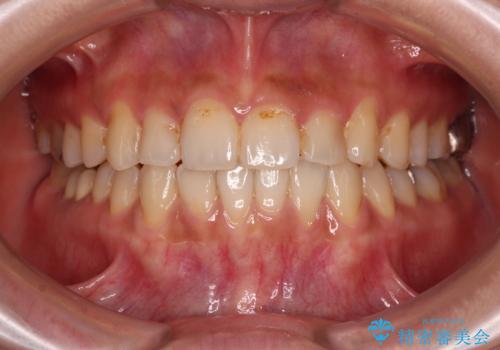

[ インビザライン矯正 ] マウスピースで治す前歯のがたつき

担当医 大元洋佑

![[ インビザライン矯正 ] マウスピースで治す前歯のがたつきの症例 治療前](https://seimitsushinbi.jp/wp/wp-content/uploads/2023/11/C7-500x350.jpg?v=1699665009)

![[ インビザライン矯正 ] マウスピースで治す前歯のがたつきの症例 治療後](https://seimitsushinbi.jp/wp/wp-content/uploads/2023/11/IMG_2993-500x350.jpg?v=1699664953)